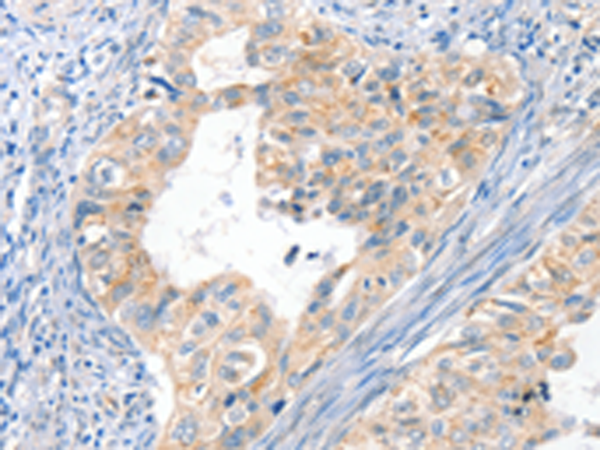

分类: 科研抗体货号: P07127别名: DTL; BAFF; BLYS; CD257; TALL1; THANK; ZTNF4; TALL-1; TNFSF20应用: IHC反应种属: Human